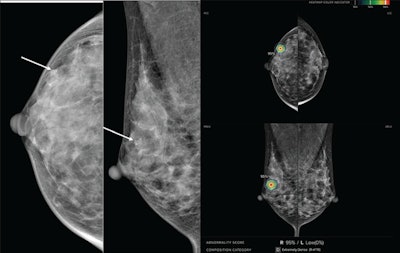

Images of a 39-year-old who underwent screening mammography. Right craniocaudal (left) and mediolateral oblique (middle) views from preoperative mammography show suspicious grouped fine pleomorphic calcifications (arrows). After biopsy showed ductal carcinoma of situ (DCIS), patient underwent breast-conserving surgery, yielding final diagnosis of ductal carcinoma in situ (intermediate grade, hormone receptor positive). (Right) Screenshot of an output of a commercial AI tool applied to preoperative mammography. AI detected right breast lesion with score of 95% on both views (concentric colored circles). Present study’s reviewing radiologist deemed AI marking to correspond with site of DCIS.Images of a 39-year-old who underwent screening mammography. Right craniocaudal (left) and mediolateral oblique (middle) views from preoperative mammography show suspicious grouped fine pleomorphic calcifications (arrows). After biopsy showed ductal carcinoma of situ (DCIS), patient underwent breast-conserving surgery, yielding final diagnosis of ductal carcinoma in situ (intermediate grade, hormone receptor positive). (Right) Screenshot of an output of a commercial AI tool applied to preoperative mammography. AI detected right breast lesion with score of 95% on both views (concentric colored circles). Present study’s reviewing radiologist deemed AI marking to correspond with site of DCIS.ARRS